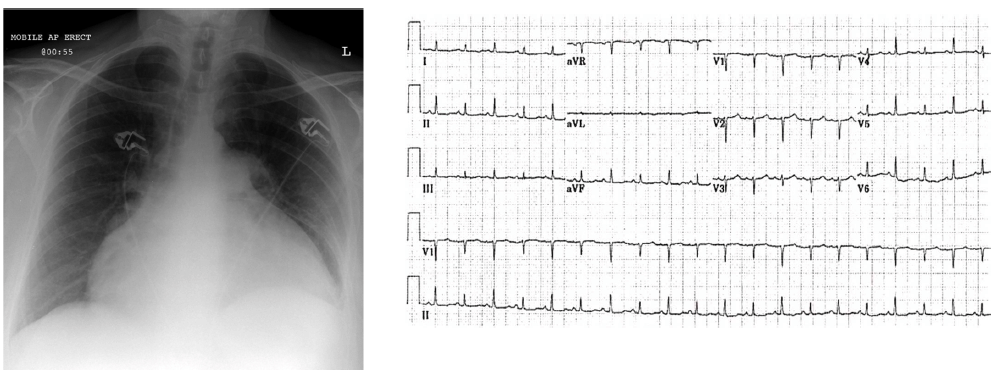

Mulher, 65 anos, chega à Emergência com história de dor torácica intensa há uma semana. Manejada em hospital do interior, foi diagnosticada com infarto do miocárdio sem estratificação invasiva. Atualmente apresenta queixa de dispneia e desconforto torácico. A paciente está fria e com sensório deprimido, apresentando PA 90/40mmHg, FC 120mmHg, turgência venosa central e mínimos estertores crepitantes em bases. Observe abaixo o RX de tórax e o ECG realizados na chegada à Emergência.

Assinale a melhor conduta a ser tomada frente a este quadro.